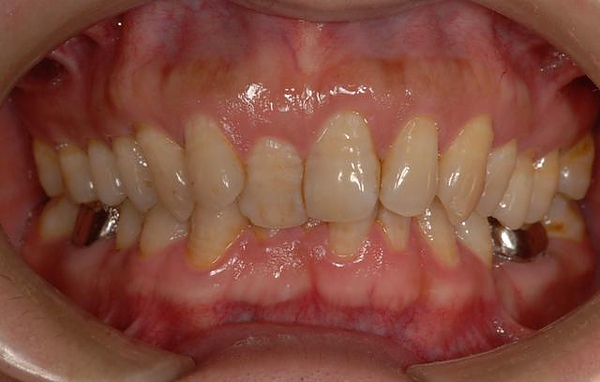

[ 矯正前 ] 治療前垂直咬合最深處是100%深咬(也就是看不見下顎門牙的意思!),通常會合併上下顎前移的擁擠,容易造成咬合性創傷(牙周組織-牙齦與齒槽骨萎縮)與清潔不易、牙齒鄰接面或深處蛀牙。學齡的小朋友若有此咬合現象,會建議提早做"早期"治療,先解除深咬、咬合創傷的嚴重性。

[齒顎矯正前-前牙擁擠加上錯(反)咬造成牙齦發炎出血與珐瑯質嚴重磨耗]